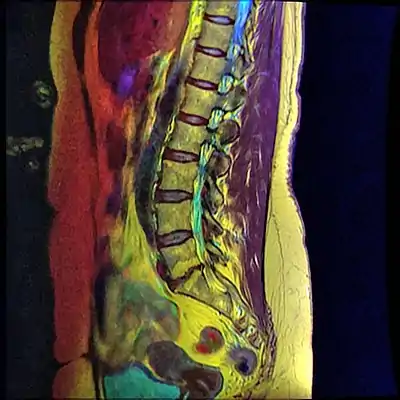

![]() | |

| Grade 1 retrolistheses of C3 on C4 and C4 on C5 | |